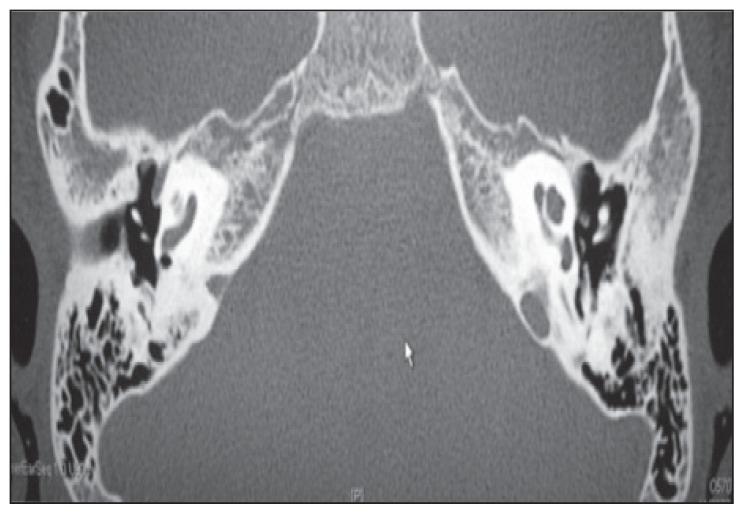

We present the first-published cochlear implant in an adolescent with sickle cell anemia (SCA) and bilateral profound sensorineural hearing loss (SNHL). A 15-year-old Saudi girl, previously diagnosed with SCA, developed gradual bilateral permanent profound SNHL over 18 months and underwent a successful cochlear implantation. SNHL associated with sickle cell crises is a well-known phenomenon. Regular hearing assessments are recommended for sickle cell patients, and early referrals for cochlear implantations are advocated for those with permanent profound SNHL.

我们首次报道了一名患有镰状细胞贫血(SCA)且双侧严重感音神经性听力损失(SNHL)的青少年接受人工耳蜗植入的病例。一名15岁的沙特女孩,之前被诊断为SCA,在18个月内逐渐出现双侧永久性严重SNHL,并成功接受了人工耳蜗植入。与镰状细胞危象相关的SNHL是一种众所周知的现象。建议对镰状细胞病患者进行定期听力评估,对于患有永久性严重SNHL的患者,提倡早期转诊进行人工耳蜗植入。